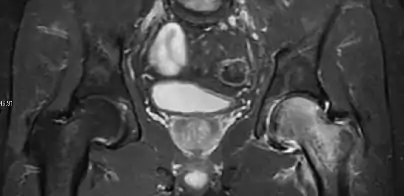

Radiological signs of transient osteoporosis of the hip include localized osteoporosis of the femoral head and neck (Figure 8). Nevertheless, final diagnosis has to be made with MRI to differentiate it from avascular necrosis and from insufficiency or stress fractures of the femoral head or neck. In case of AVN, radiographs can only demonstrate delayed or advanced signs. Staging according to Ficat classification ranges between normal appearance (stage I), slight increased density in the femoral head (stage II), subchondral collapse of the femoral head with or without “crescent” sign (stage III), and advanced collapse with secondary osteoarthritis (stage IV). In the case of stress or insufficiency fractures X-ray sensitivity has been proven to be much lower than MRI, which is currently the gold standard.[1]

Figure 8:

- X-ray of a patient with transient osteoporosis of the left hip showing osteoporosis.[1]

- Coronal stir imaging in transient osteoporosis, showing diffuse edema.[1]

- Scintigraphy (A), sagittal T1 (B), and coronal PD fat sat of a patient with a subchondral fracture of the femoral head with convex shape to the articular surface.[1]

- Coronal T1 of a patient with avascular necrosis of the femoral head.[1]